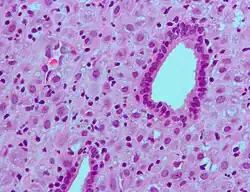

Metabolism

The metabolism of progesterone is rapid and extensive, and it occurs mainly in the liver,[112][113][114] though enzymes that metabolize progesterone are also expressed widely in the brain, skin, and various other extrahepatic tissues.[77][115] Progesterone has an elimination half-life of only approximately five minutes in circulation.[112] The metabolism of progesterone is complex, and it may form as many as 35 different unconjugated metabolites when it is ingested orally.[114][116] Progesterone is highly susceptible to enzymatic reduction via reductases and hydroxysteroid dehydrogenases because of its double bond (between the C4 and C5 positions) and its two ketones (at the C3 and C20 positions).[114]

The major metabolic pathway of progesterone is reduction by 5α-reductase[77] and 5β-reductase, into the dihydrogenated 5α-dihydroprogesterone and 5β-dihydroprogesterone, respectively.[113][114][117][118] This is followed by the further reduction of these metabolites via 3α-hydroxysteroid dehydrogenase and 3β-hydroxysteroid dehydrogenase into the tetrahydrogenated allopregnanolone, pregnanolone, isopregnanolone, and epipregnanolone.[119][113][114][117] Subsequently, 20α-hydroxysteroid dehydrogenase and 20β-hydroxysteroid dehydrogenase reduce these metabolites to form the corresponding hexahydrogenated pregnanediols (eight different isomers in total),[113][118] which are then conjugated via glucuronidation and/or sulfation, released from the liver into circulation, and excreted by the kidneys into the urine.[112][114] The major metabolite of progesterone in the urine is the 3α,5β,20α isomer of pregnanediol glucuronide, which has been found to constitute 15–30% of an injection of progesterone.[17][120] Other metabolites of progesterone formed by the enzymes in this pathway include 3α-dihydroprogesterone, 3β-dihydroprogesterone, 20α-dihydroprogesterone, and 20β-dihydroprogesterone, as well as various combination products of the enzymes aside from those already mentioned.[17][114][120][121] Progesterone can also first be hydroxylated (see below) and then reduced.[114] Endogenous progesterone is metabolized approximately 50% into 5α-dihydroprogesterone in the corpus luteum, 35% into 3β-dihydroprogesterone in the liver, and 10% into 20α-dihydroprogesterone.[122]

Relatively small portions of progesterone are hydroxylated via 17α-hydroxylase (CYP17A1) and 21-hydroxylase (CYP21A2), into 17α-hydroxyprogesterone and 11-deoxycorticosterone (21-hydroxyprogesterone), respectively,[116] and pregnanetriols are formed secondarily to 17α-hydroxylation.[123][124] Even smaller amounts of progesterone may also be hydroxylated via 11β-hydroxylase (CYP11B1) and, to a lesser extent, via aldosterone synthase (CYP11B2) into 11β-hydroxyprogesterone.[125][126][44] In addition, progesterone can be hydroxylated in the liver by other cytochrome P450 enzymes that are not steroid-specific.[127] Catalyzed mainly by CYP3A4, 6β-Hydroxylation is the major transformation and is responsible for approximately 70% of cytochrome P450-mediated progesterone metabolism.[127] Other routes include 6α-, 16α-, and 16β-hydroxylation.[114] However, treatment of women with ketoconazole (a strong CYP3A4 inhibitor) had minimal effects on progesterone levels, producing only a slight and non-significant increase, suggesting that cytochrome P450 enzymes play only a small role in progesterone metabolism.[128]